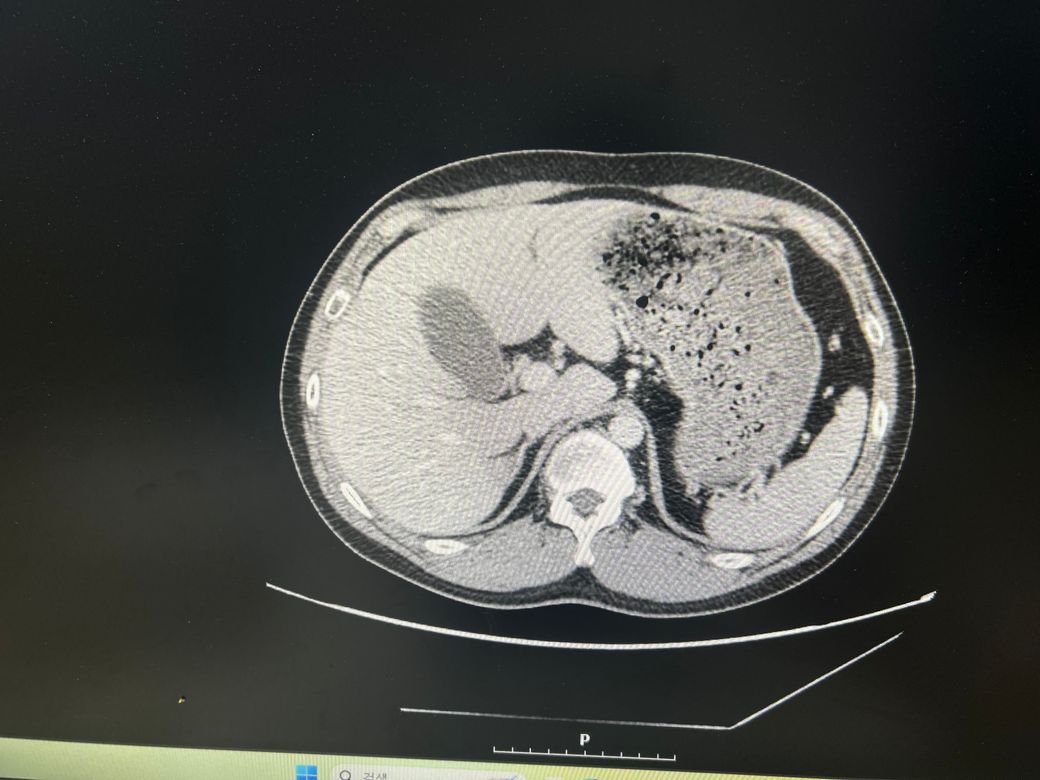

담낭염일 까요?? (CT 사진 있어요)

우상복부 통증(좌상복부 통증도 생김), 오른쪽 어깨에서 허리까지통증, 소화불량, 팽만감,답답함, 설사 증상이 있는데..... 담낭염이 맞을까요?

• 3번 째 사진

CT에서 담낭염은 담낭벽이 두꺼워보이고 벽이 조영증강되는데

환자분 자료의 경우 그런 소견이 뚜렷하게 보이지는 않는 것 같습니다.

• 애매합니다. 담낭의 크기가 다소 늘어나 보이긴 합니다만, 당남염을 강력하게 의심할만한 다른 소견들이 보이지는 않습니다. 가령 담낭의 벽이 두꺼워지거나 담낭 주변의 염증 소견, 담낭 목을 막고 있는 담석 등이 따로 관찰되거나 하지는 않기 때문에 담낭염을 강력하게 의심하기는 어려워 보입니다. 우상복부의 압통 및 머피징후 등의 신체검진 소견이 있다면 담낭염의 가능성을 고려해볼 수 있겠습니다만, 해당 CT 소견만으로는 판단하기 어렵습니다.

첨부해주신 CT 영상에는 담낭 주변에 두드러지는 염증소견이 관찰되지 않습니다. 다만 영상의 모든 단면을 확인한 것이 아니라서 담석증의 여부에 대해서는 확답드릴 수 없습니다. 증상이 지속되면 내과에서 진료를 받아보시는 것을 권해드립니다.